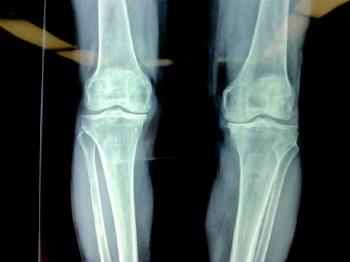

对膝关节骨性关节炎、股骨头坏死的治疗,采用分阶段阶梯治疗方案,包括保守运动康复疗法,中医中药疗法、生长因子注射、关节镜清理、半月板成形、截骨矫形、单髁置换、全膝关节置换等一系列疗法。

手术前

手术前后对比。

手术后